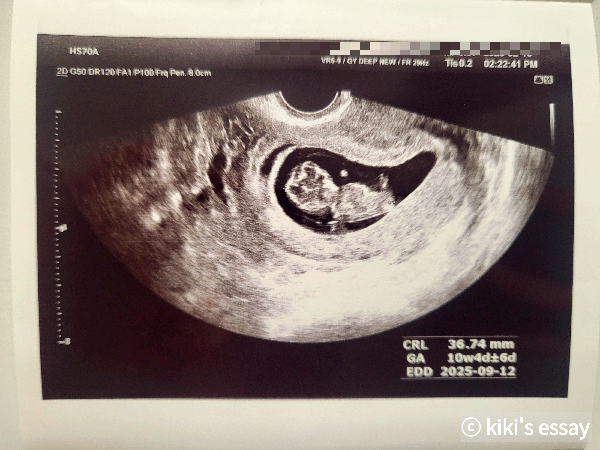

3.67cm

일주일 만에 만난 금동이는 키가 1.1cm나 커 있었다.

초음파를 보던 담당의는

"10주 2일이 아닌데? 어휴 그보다 큰데요? 잘 크고 있네~"

라며 놀라워했다.

"관절이 생겼어요. 이게 팔이고, 이게 무릎이에요."

이 화면과 이 사진을 부둥켜안고 일주일 내내 어찌나 소중히 다뤘는지 모른다.

무릎이라니, 관절이라니 … 너무 하찮고 귀엽고 소중하다.

동영상을 볼 때마다 신기하고, 놀라운 건 금동이의 심장이 뛸 때마다 반짝반짝거린다는 점이다. 명확하고 또렷한 반짝거림이 마치 "엄마 나 여기 있어용!" 하고 외치는 것만 같아서 가슴이 찡하다. 분당 174번이나 뛰는 심장소리는 더할 나위 없이 내 심장을 후려 팬다.